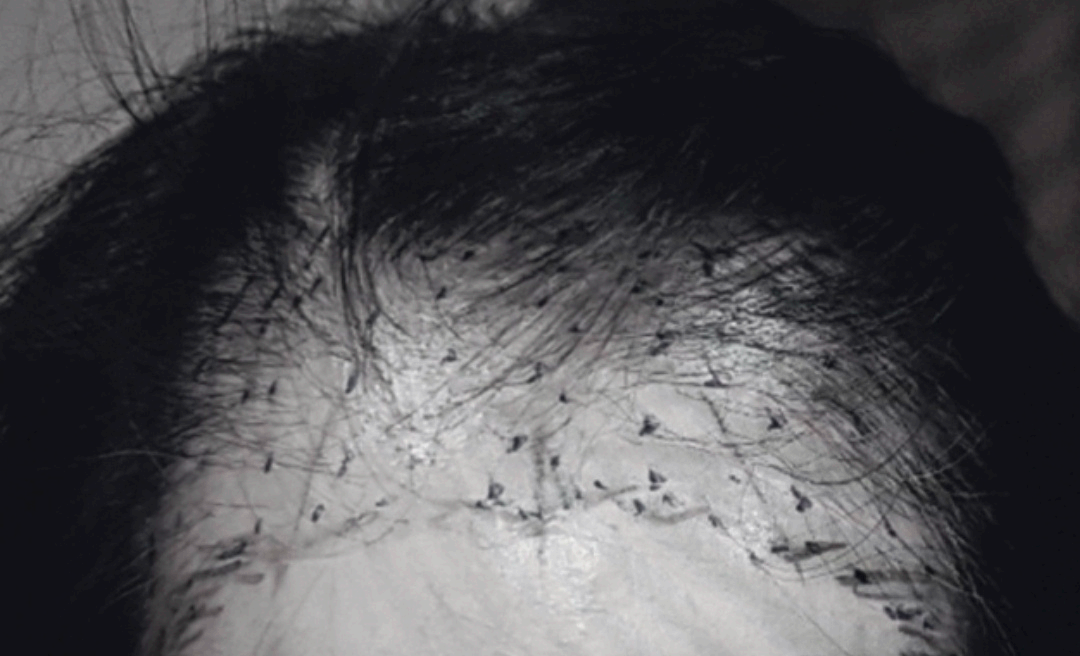

3. 전두부 섬유화 탈모증

영어로는 frontal fibrosing alopecia라고 하는 질환으로 비교적 드문 질환이라고 해요. 흔한 질환은 아니어서 피부과 전문의가 아니라면 감별이 어려울 수 있는데요. 이 전두부 섬유화 탈모증은 주로 폐경기 이후에 여성에게서 발생하고 전두부와 측두부의 헤어라인이 퇴축되면서 흉터처럼 딱딱하게 변하면서 머리카락이 빠지는 질환입니다.

점차 진행하는 질환이고 여러 치료 방법들이 제시되고는 있지만 안타깝게도 치료가 어려운 질환이고 아직까지도 명확하고 스탠다드한 치료법은 없는 실정이라해요.